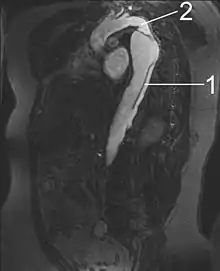

MRI

Magnetic resonance imaging (MRI) is also used for the detection and assessment of aortic dissection, with a sensitivity of 98% and a specificity of 98%. An MRI examination of the aorta produces a three-dimensional reconstruction of the aorta, allowing the physician to determine the location of the intimal tear and the involvement of branch vessels, and to locate any secondary tears. It is a noninvasive test, does not require the use of iodinated contrast material, and can detect and quantitate the degree of aortic insufficiency.

The disadvantage of the MRI scan in the face of aortic dissection is that it may be available only in larger hospitals, and the scan is relatively time-consuming, which could be dangerous in people who are already very unwell. Due to the high-intensity magnetic fields used during MRI, it cannot be used on individuals with metallic implants. In addition, some individuals experience claustrophobia while surrounded by the MRI magnet.